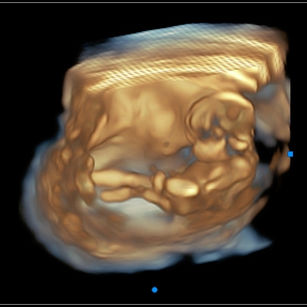

16 Weeks Pregnant

Size: ~4.5 inches (11.5 cm), the size of an Avocado!

16 Weeks 4 Days Pregnant